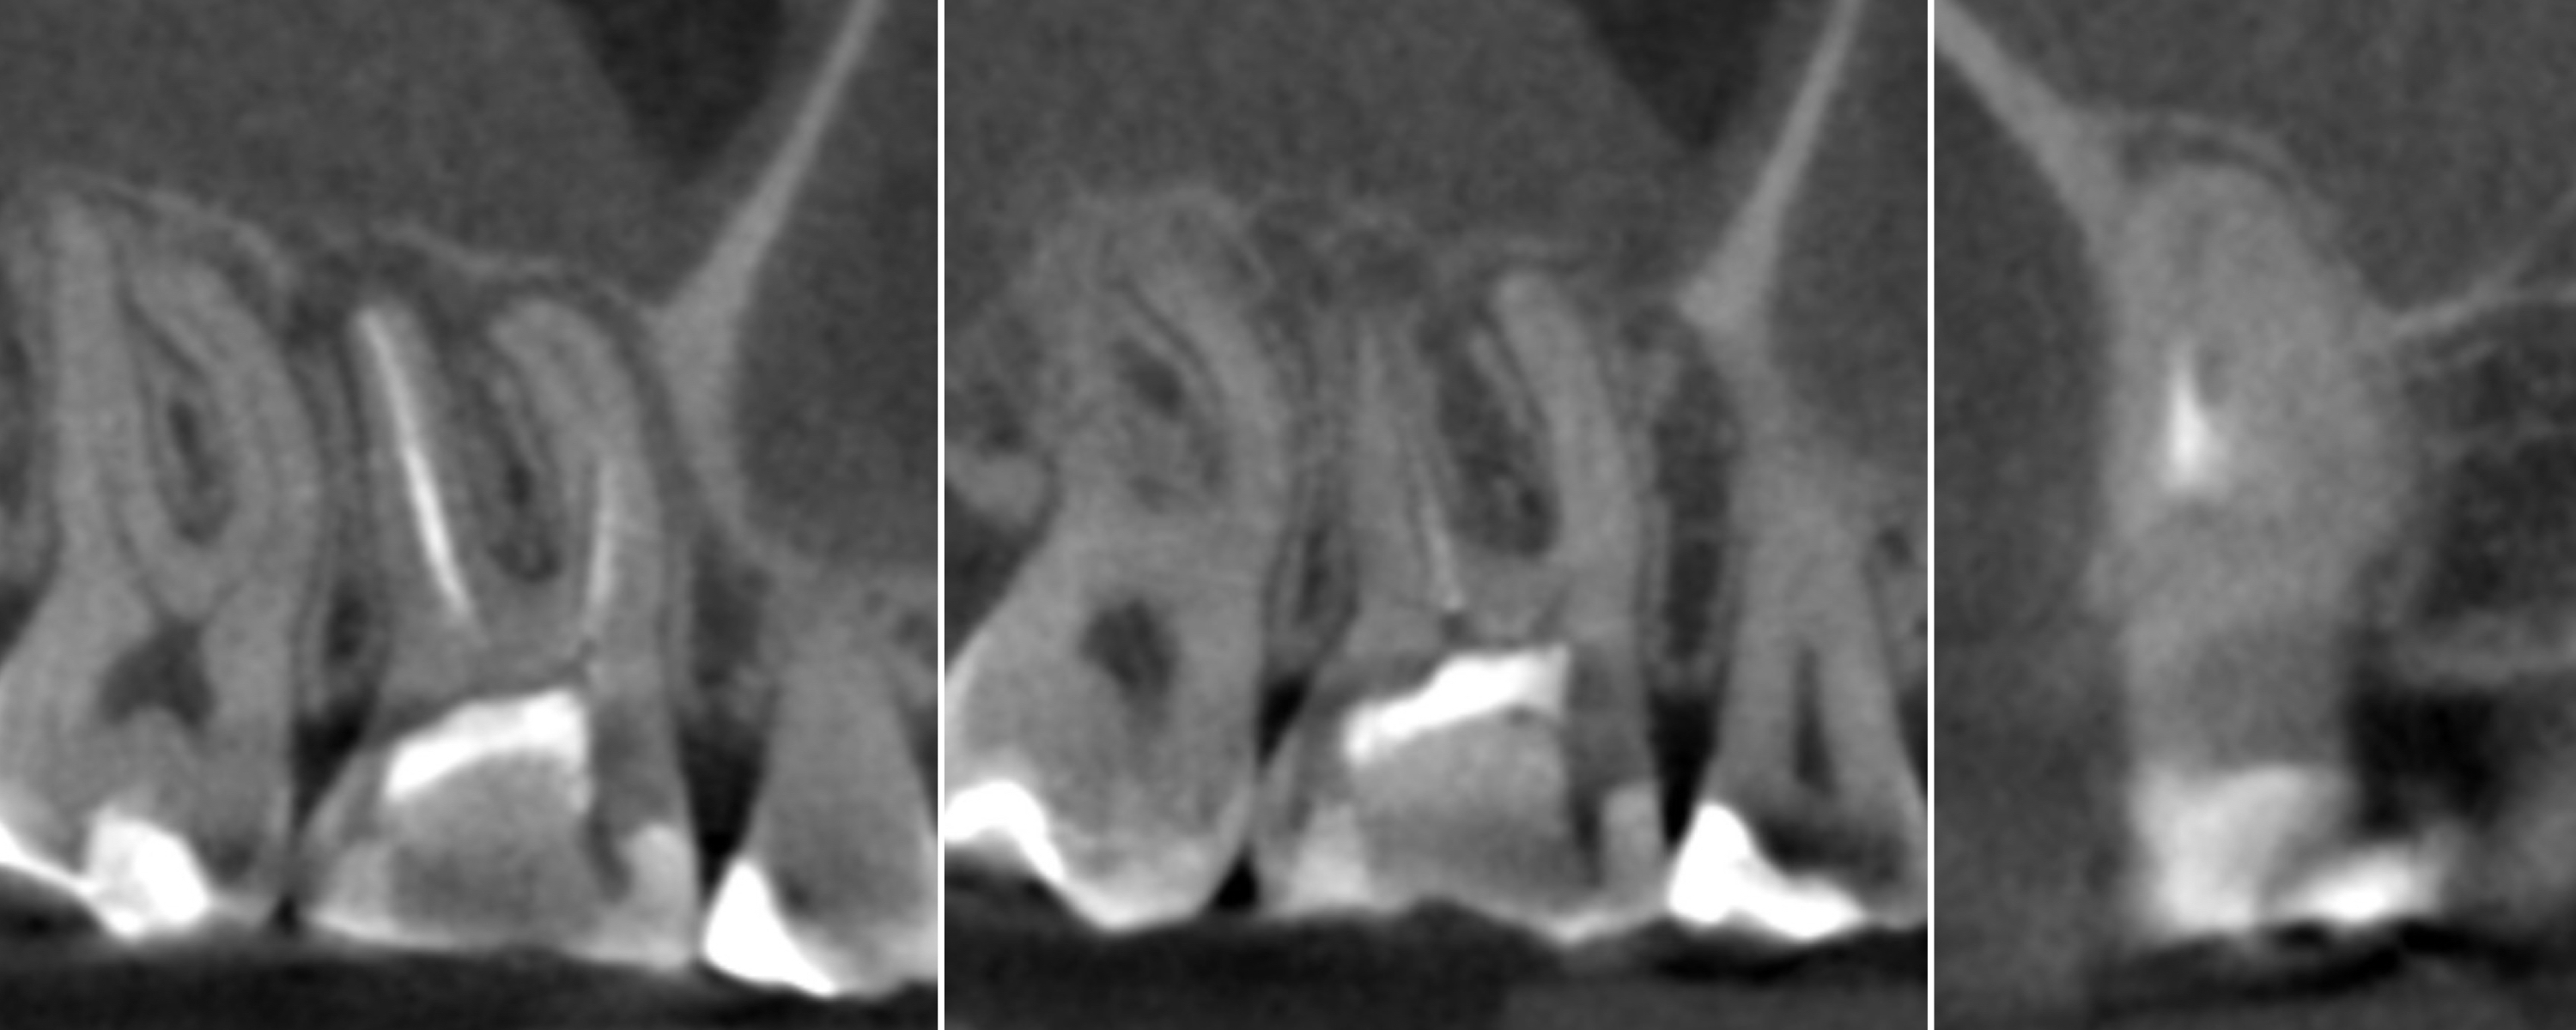

A 40-year-old female patient was referred to Dr Karaś’s office because tooth #47 was symptomatic and tender to percussion. During examination with a conventional radiograph, the referring dentist could not find any visible signs of the root canals, so he would not have been able to shape the root canals properly.

During the consultation appointment, a CBCT scan was performed. It revealed a small osteolytic lesion around the mesial root, suggesting the possibility of achieving patency in the root canals in the mesial root. Around the distal root, there were no signs of the lesion, which indicated that the mesial root was the cause of the symptoms. The radiographic examination also revealed a broken lentulo in the MB canal (Fig. 16).

Figs. 16 a & b